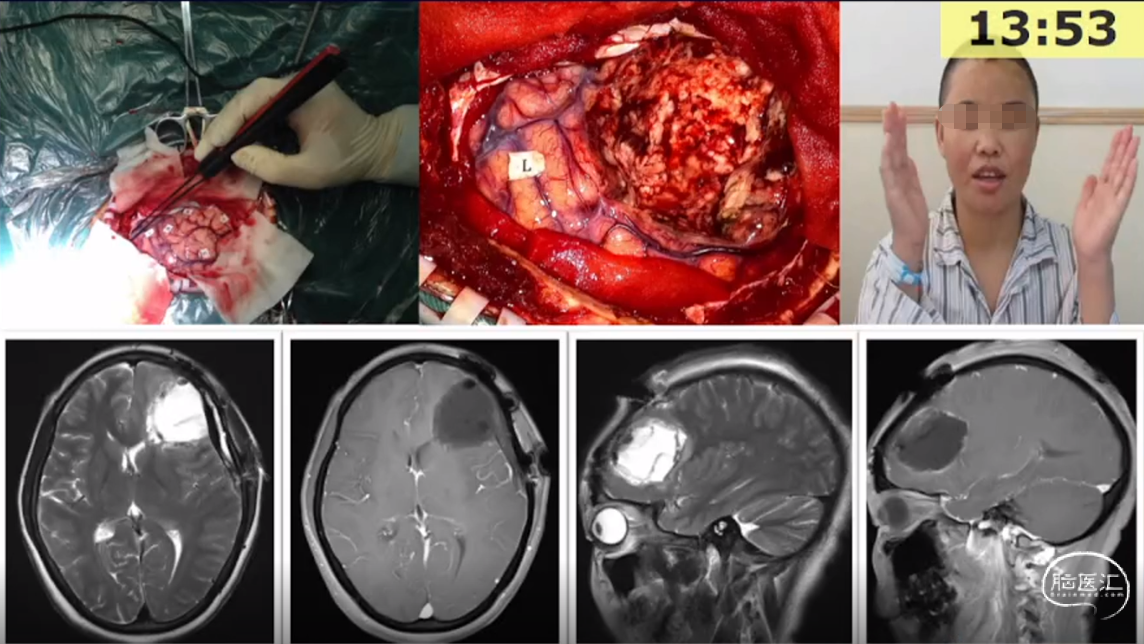

刘宏毅教授:脑网络的构建及在脑胶质瘤诊疗中应用初探

讲题:脑网络的构建及在脑胶质瘤诊疗中应用初探